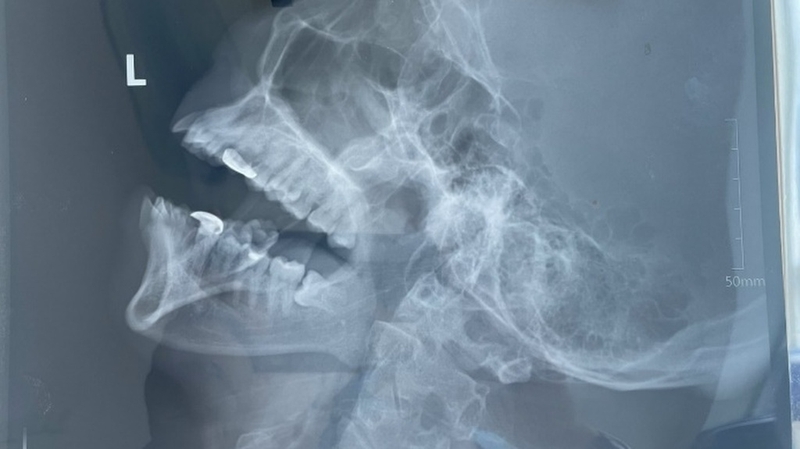

X-quang hàm chếch là một kỹ thuật hình ảnh y khoa quan trọng, giúp bác sĩ chẩn đoán và điều trị nhiều vấn đề liên quan đến vùng hàm mặt. Bài viết này sẽ giúp bạn hiểu rõ hơn về X-quang hàm chếch, từ quy trình thực hiện cho đến những lợi ích và hạn chế của nó.

Chụp X-quang hàm chếch là một phương pháp chẩn đoán hình ảnh tiên tiến, sử dụng tia X để tạo ra hình ảnh chi tiết và ba chiều của cấu trúc xương hàm, răng và các mô mềm xung quanh. Kỹ thuật này cho phép các nha sĩ có thể nhìn thấy những khu vực mà các phương pháp X-quang truyền thống như X-quang toàn cảnh hoặc X-quang cận chóp không thể hiển thị rõ ràng.

Hình ảnh từ X-quang hàm chếch cung cấp cái nhìn toàn diện về tình trạng răng miệng, giúp phát hiện các vấn đề như sâu răng, nhiễm trùng, u bướu và các dị dạng xương hàm. Phương pháp này đóng vai trò quan trọng trong việc chẩn đoán chính xác và nhanh chóng, hỗ trợ lập kế hoạch điều trị hiệu quả hơn. Với sự phát triển của công nghệ, chụp X-quang hàm chếch ngày càng trở nên an toàn hơn cho bệnh nhân, giảm thiểu tối đa mức độ phơi nhiễm tia X.